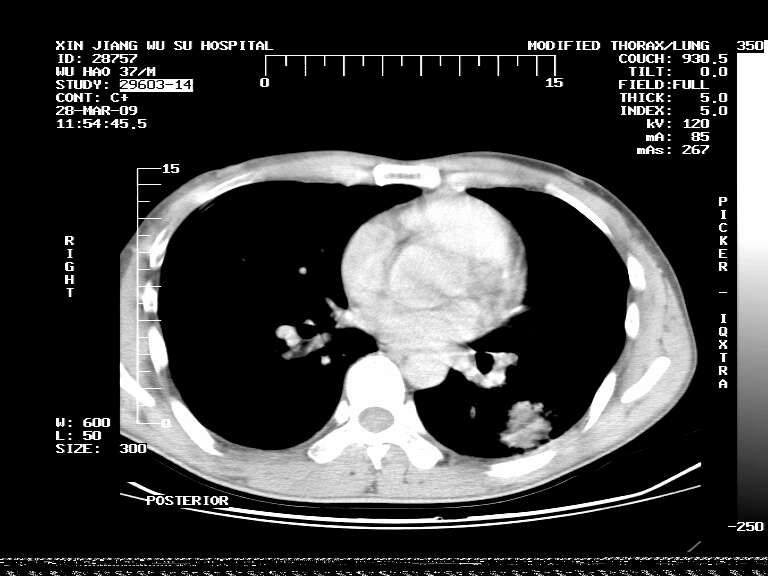

男,37岁,体检胸透发现阴影。

患者体检发现 无症状 左肺下叶占位,边缘模糊,可见血管聚束、分叶、胸膜牵拉,增强呈不均匀性强化。 首先考虑左肺下叶周围型肺癌,建议穿刺活检。

患者体检发现 无症状 左肺下叶占位,边缘模糊,可见血管聚束、分叶、胸膜牵拉,增强呈不均匀性强化。 首先考虑左肺下叶周围型肺癌,建议穿刺活检。支持!

左肺下叶见一结节病变,边缘欠清不光滑,与胸膜粘连且胸膜局限性增厚,注药后呈环形强化,动脉期壁呈明显点环状强化,静脉期壁强化减低,中心密度低无强化,灶周无明显的卫星灶和水肿区(晕征)---考虑周围性肺癌,不除外感染性病变,建议穿刺活检。

左肺下叶软组织病灶,密度较高,内见点状钙化,其周围见子灶,邻近胸膜扁平样增厚.c+病灶强化明显,中心强化弱.诊断:左肺下叶结核瘤.

左肺下叶大片实变影,内靠胸膜见不规则更高密度结节灶,边缘强化,相邻胸膜增厚,胸膜下脂肪线存在。考虑炎症,结核可能。